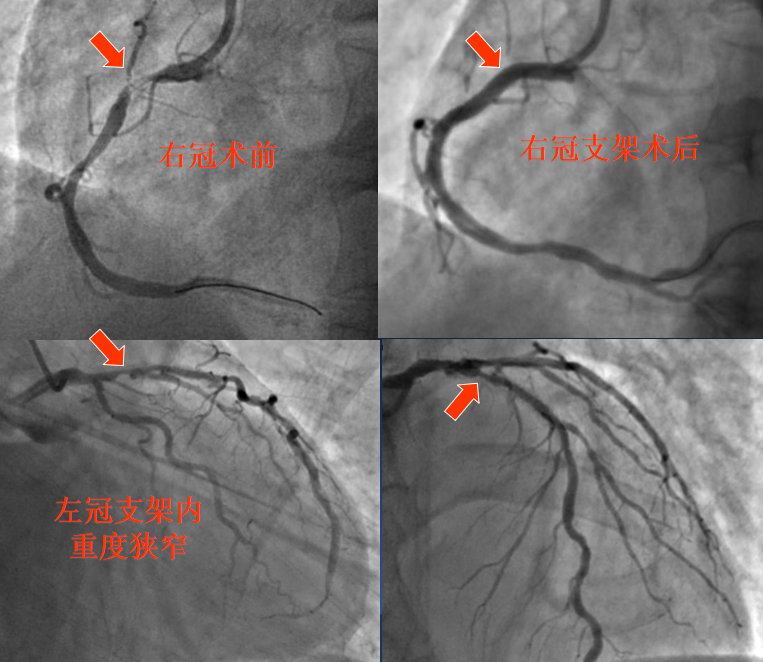

72岁的杨大爷是一位多年冠心病患者,18年前因患急性心肌梗死于当地医院行介入治疗植入支架。 2个月前又出现严重的胸闷、胸痛症状,转至我院冠心病二病区,经检查诊断为急性非ST段抬高型心梗。2022-06-29为患者进行冠脉造影复查,结果显示:左主干及多支血管病变合并严重钙化,其中前降支原支架内80-90%再狭窄;右冠状动脉95%狭窄,先对右冠状动脉病变行支架植入治疗,因患者病情复杂,计划1月后再次治疗左冠状动脉严重病变。

8月1日手术团队再次为患者进行介入治疗,但这次手术并不顺利,术中造影及血管内超声(IVUS)检查均提示:左主干-前降支近中段严重钙化病变,局部钙化达到270°,但考虑患者为支架内再狭窄,使用旋磨技术治疗手术风险高,可能发生严重并发症,故改为应用高压球囊及切割球囊进行充分预扩张处理,于病变处再次植入支架,但新问题接踵而至,术中发现支架植入后使用后扩张球囊反复高压扩张均不能使支架充分膨胀,出现棘手的“狗骨头征”,复查血管内超声显示:再次植入的支架局部膨胀不全,最小管腔面积仅为2.65mm2,且支架外侧仍存在严重钙化环,因手术时间较长,考虑患者安全,遂暂时结束手术。但这样的手术结果远未达到满意的疗效,且有血栓形成威胁患者生命的风险。冠心病中心对此特殊病例高度重视,在北阜专家叶绍东教授、崔成教授和齐峰教授亲自主持下专门针对后续治疗方案进行了充分分析讨论,专家们一致认为可以考虑使用目前最先进的冠脉血管内冲击波球囊来解决患者的这一难题。